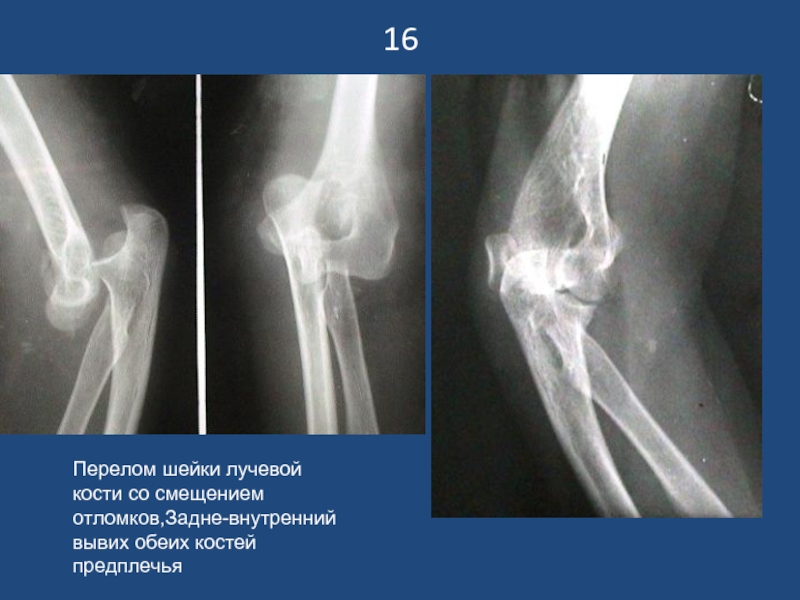

Слайд 1716

Перелом шейки лучевой кости со смещением отломков,Задне-внутренний вывих обеих костей предплечья